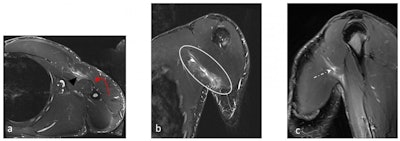

Although rare in the general population, "pec tears" (pectoralis major rupture) are relatively common in weightlifters and bodybuilders, the authors wrote. The injury is commonly incomplete rupture of the myotendinous junction of the sternal head. A complete tear of its tendinous attachment is less common. MRI is excellent at diagnosing these injuries considering optimizing the field-of-view and acquisition angles to fully visualize the muscle and its tendon.

Rupture of the biceps tendon is more common, and proximal rupture of the long-head tendon has also been reported. "Both ultrasound and MRI are helpful in determining biceps rupture, whether partial or complete, tendon retraction, the presence of hematoma, myotendinous junction, and muscle belly and importantly assessment of associated injuries like rotator cuff tendon or labrum tears."

In active athletes, continuous sliding movement of the scapula over the rib cage result in soft tissues irritation at the scapulothoracic space that might manifest as bursitis, they noted. "A subsequent audible or palpable click might be encountered in what is described as 'snapping scapula syndrome.' The latter also includes various underlying anatomical and mechanical etiologies encompassing variations in the anatomy of the scapula bone, periscapular muscles dyskinesia, and space-occupying lesions."